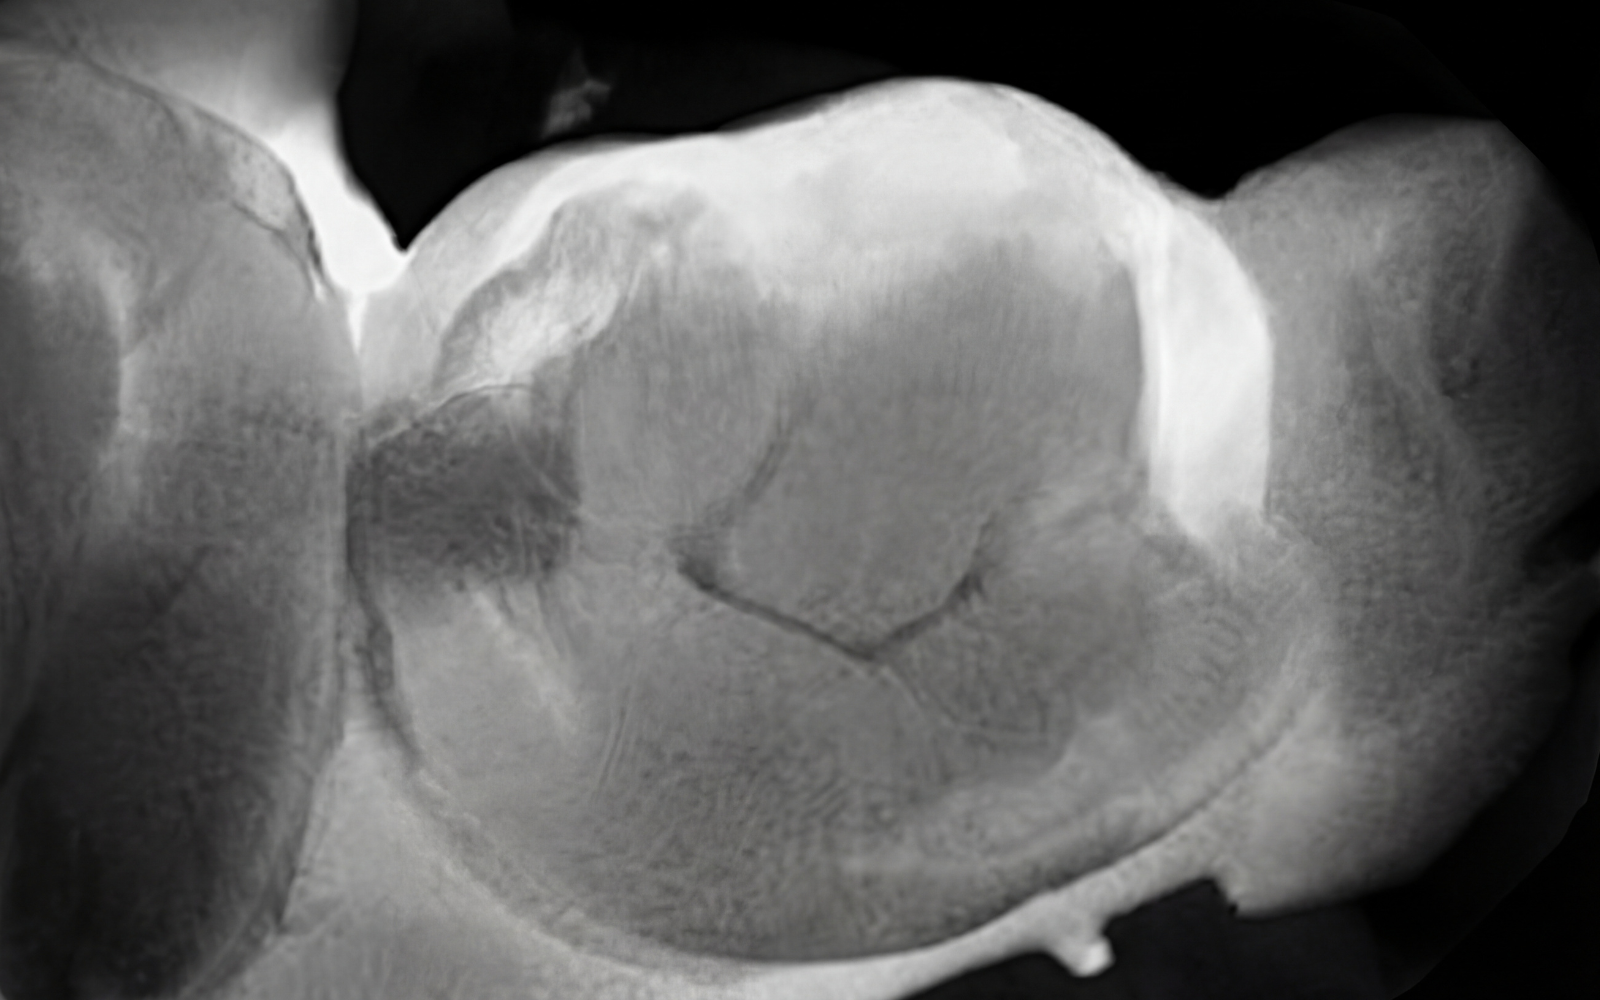

Lorsque cela est possible, nous utilisons la Diagnocam, une caméra permettant le diagnostic précoce des caries débutantes, de manière non irradiante.

Cette méthode repose sur la transillumination (laser à une longueur d’onde de 780 nm).